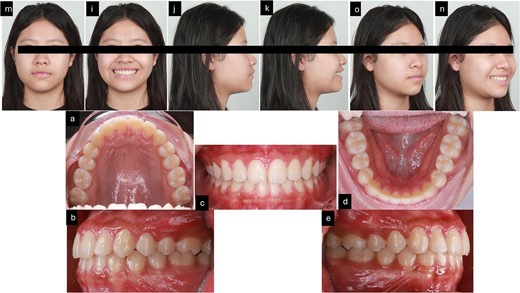

After 16 months of orthodontic treatment, all treatment objectives were successfully accomplished. This resulted in a well-aligned dentition with all spaces closed, leading to enhanced facial aesthetics, and retracted upper incisors. The overbite and overjet were within normal ranges, achieving a Class I occlusion. There was also a visibly reduced GS after treatment. The superimposition and cephalometric analysis table before and after treatment showed significant improvements in profile and incisor inclination, the clear aligner removable appliance was used for retention (Figs 5 and 6, and Table 1). After 2 weeks of periodontal surgery, the patient’s gingival line has healed exceptionally well. It now wraps around the tooth roots in a scalloped shape, with no black triangles or exposed tooth roots. The surgery also fixed the patient’s GS, resulting in an ideal gingival exposure. As a result, the crowns of the teeth are more visible and stable up to 3 months (Fig. 7).

Post-treatment records. (a–f) Extra oral pictures post-treatment; (g–t) post-treatment radiographies; o: superimposition before and after treatment; (i–n) intraoral pictures post-treatment.

3 months follow-up after treatment. (m–n) Extra oral pictures; (a–e) intraoral pictures.